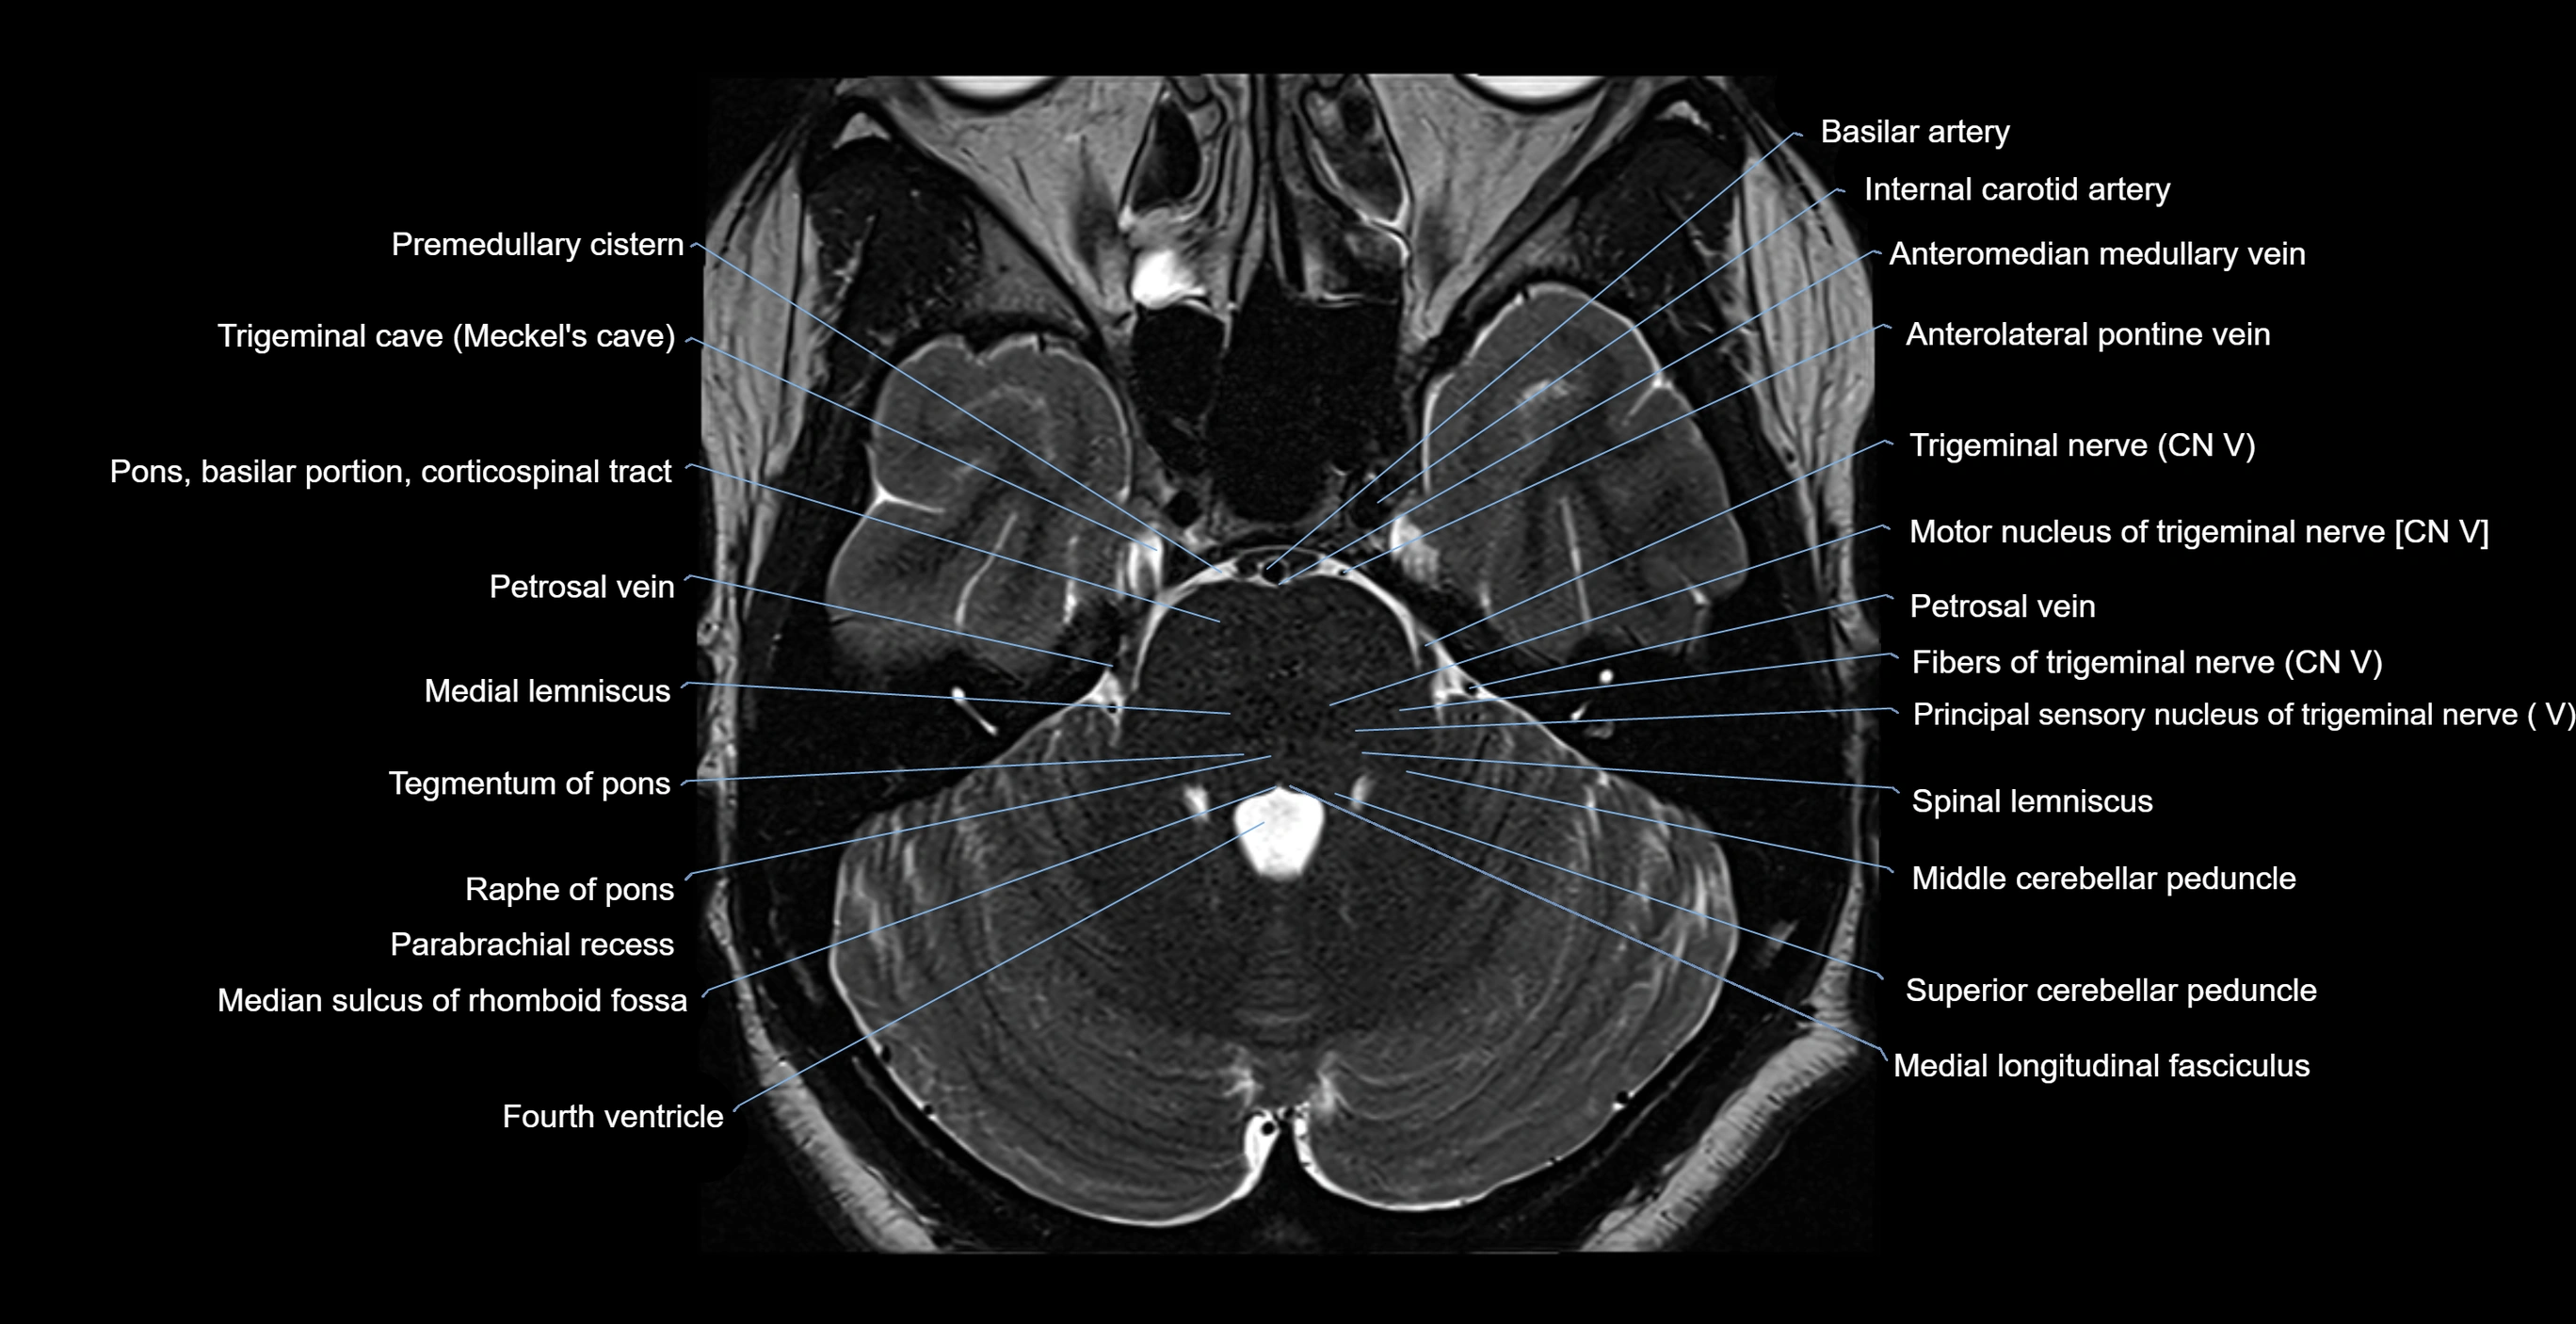

- Anterolateral pontine vein

- Fibers of trigeminal nerve

- Medial lemniscus

- Medial longitudinal fasciculus

- Middle cerebellar peduncle

- Motor nucleus of trigeminal nerve

- Parabrachial recess

- Petrosal vein

- Principal sensory nucleus of the trigeminal nerve

- Principal sensory nucleus of trigeminal nerve

- Spinal lemniscus

- Superior cerebellar peduncle